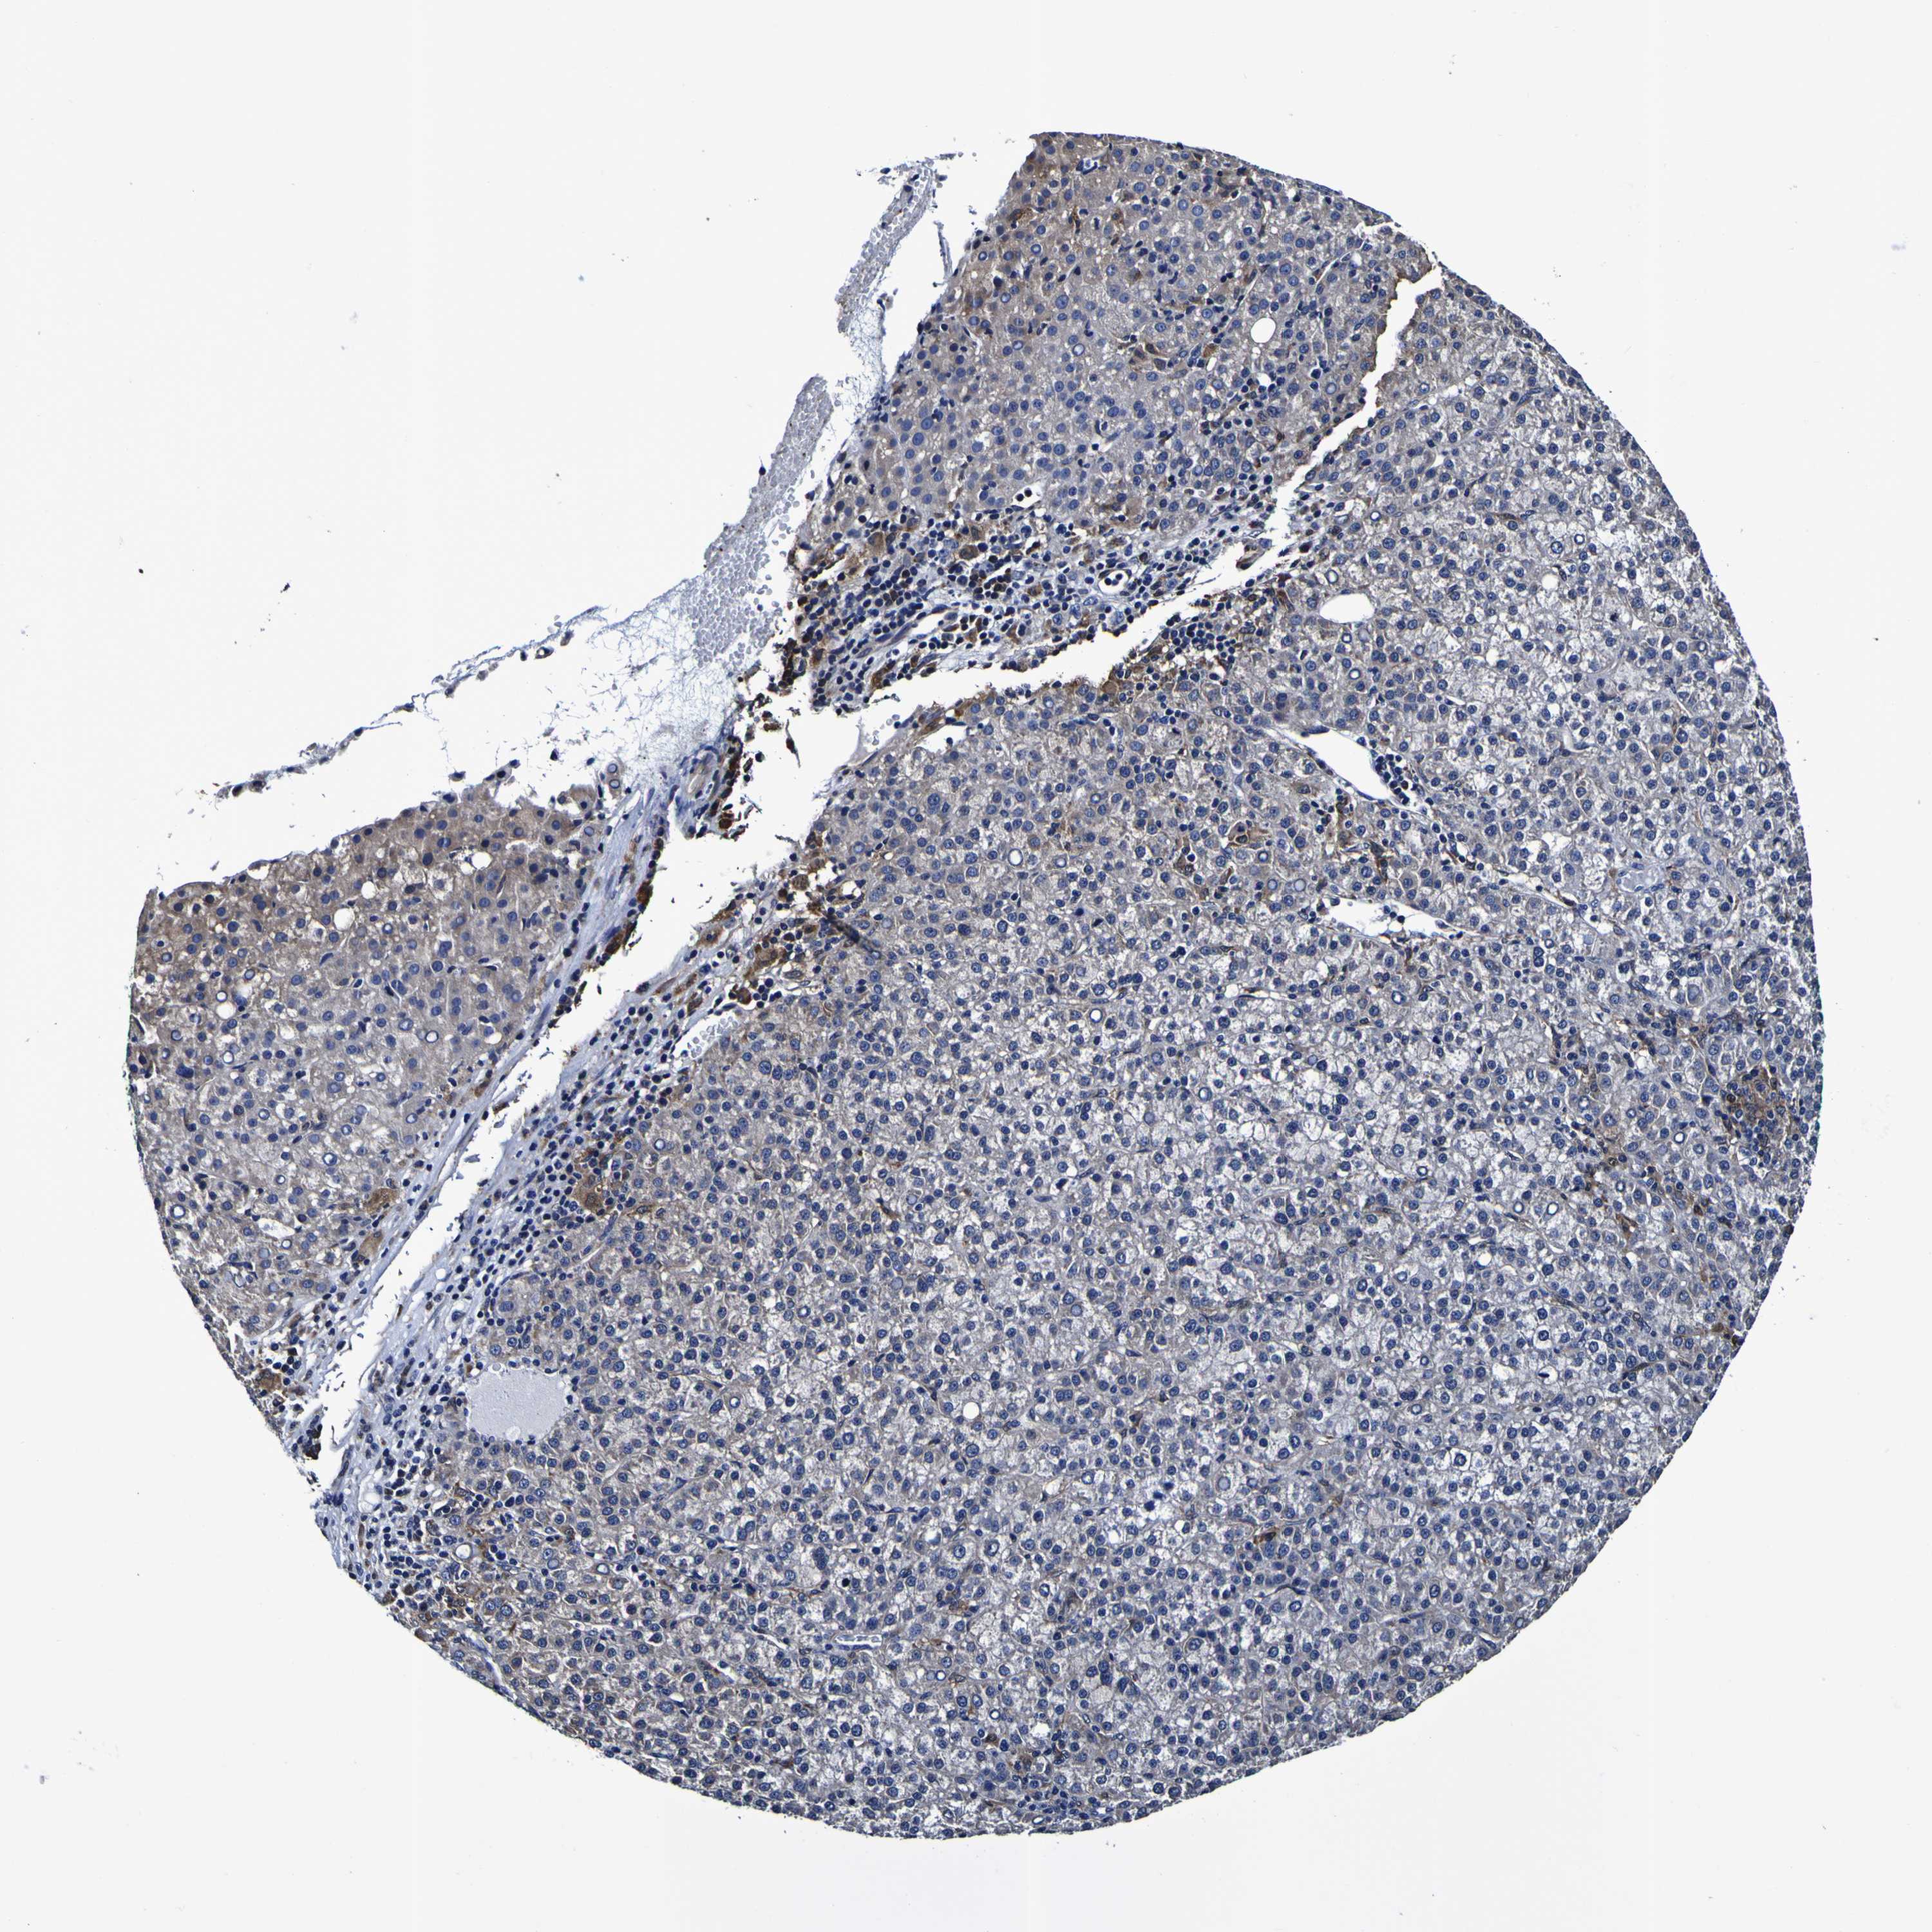

LIVER CANCER - Protein expressioni

A mouse-over function shows sample information and annotation data. Click on an image to view it in a full screen mode. Samples can be filtered based on level of antibody staining by selecting one or several of the following categories: high, medium, low and not detected. The assay and annotation is described here.

Note that samples used for immunohistochemistry by the Human Protein Atlas do not correspond to samples in the TCGA dataset.

Antibody stainingi

Antibody staining in the annotated cell types in the current human tissue is reported as not detected, low, medium, or high, based on conventional immunohistochemistry profiling in selected tissues. This score is based on the combination of the staining intensity and fraction of stained cells.

Each image is clickable and will lead to virtual microscopy that enables deeper exploration of all samples and also displays staining intensity scores, fraction scores and subcellular localization as well as patient and tissue information for each sample.

Antibody HPA044758

Antibody CAB011582

Staining

High

Medium

Low

Not detected

Intensity

Strong

Moderate

Weak

Negative

Quantity

>75%

75%-25%

<25%

None

Location

Nuclear

Cytoplasmic/membranous

Cytoplasmic/membranous,nuclear

Cholangiocarcinoma

Carcinoma, Hepatocellular, NOS